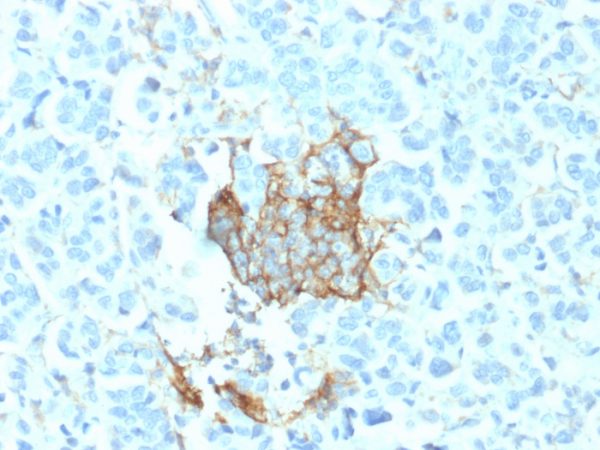

Formalin-fixed, paraffin-embedded human Adrenal Gland stained with NGFR Mouse Monoclonal Antibody (NGFR/1964).